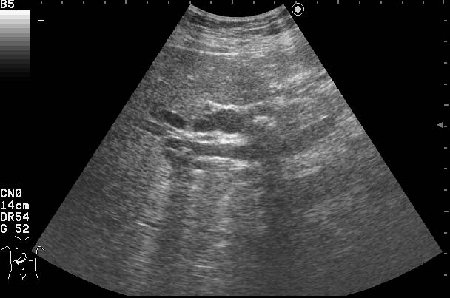

Сонограммы холедоха:

- Продольный скан холедоха

На верхнем снимке можно предположить внутрипросветную опухоль в холедохе.

В сущности, ответ правильный уже был - это опухоль холедоха с инкрустацией ее ткани.

Благодаря такой необычной презентации опухоль была ошибочно принята за камень холедоха.

Спасибо!Очень интересный случай,смотрю уже который раз.Можно ошибиться,но "камень"обволочен мягкотканной структурой-гипоэхогеной,раздвигая стенки коледоха,типа "веретено".Так,что коллега права-опухоль